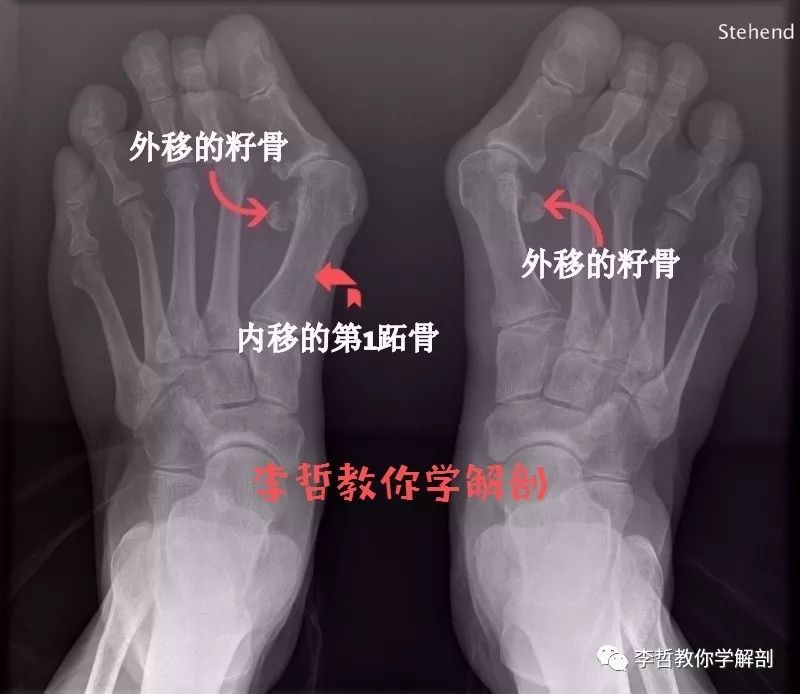

拇外翻是指大拇趾向外侧偏移和旋转,跖骨向内。

与此同时,第一跖骨的内移改变了他和位于其下籽骨的关系。由于籽骨稳固的固定在其他结构上,第一趾骨的内移,令籽骨移向外侧。

这样的生物力学改变,导致拇指周围的肌肉整体移向外侧。肌肉一收缩拇指就会更加向外偏移。加速姆外翻的恶化。